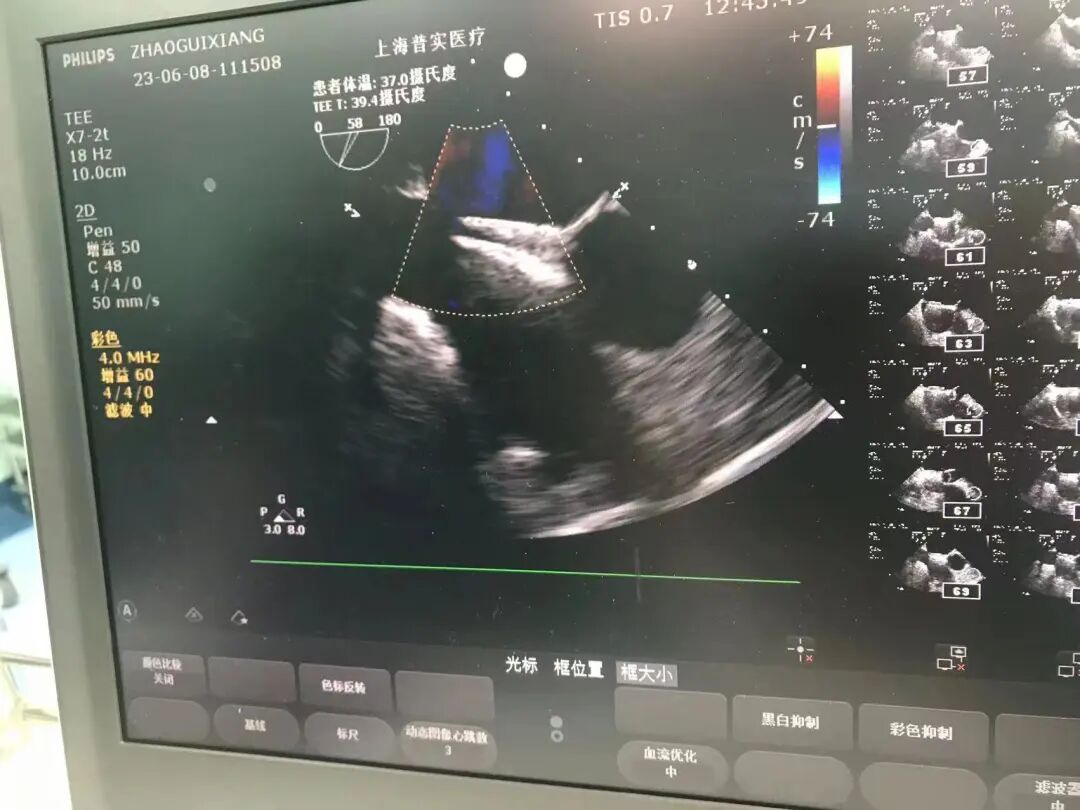

食道超声精准引导并定位